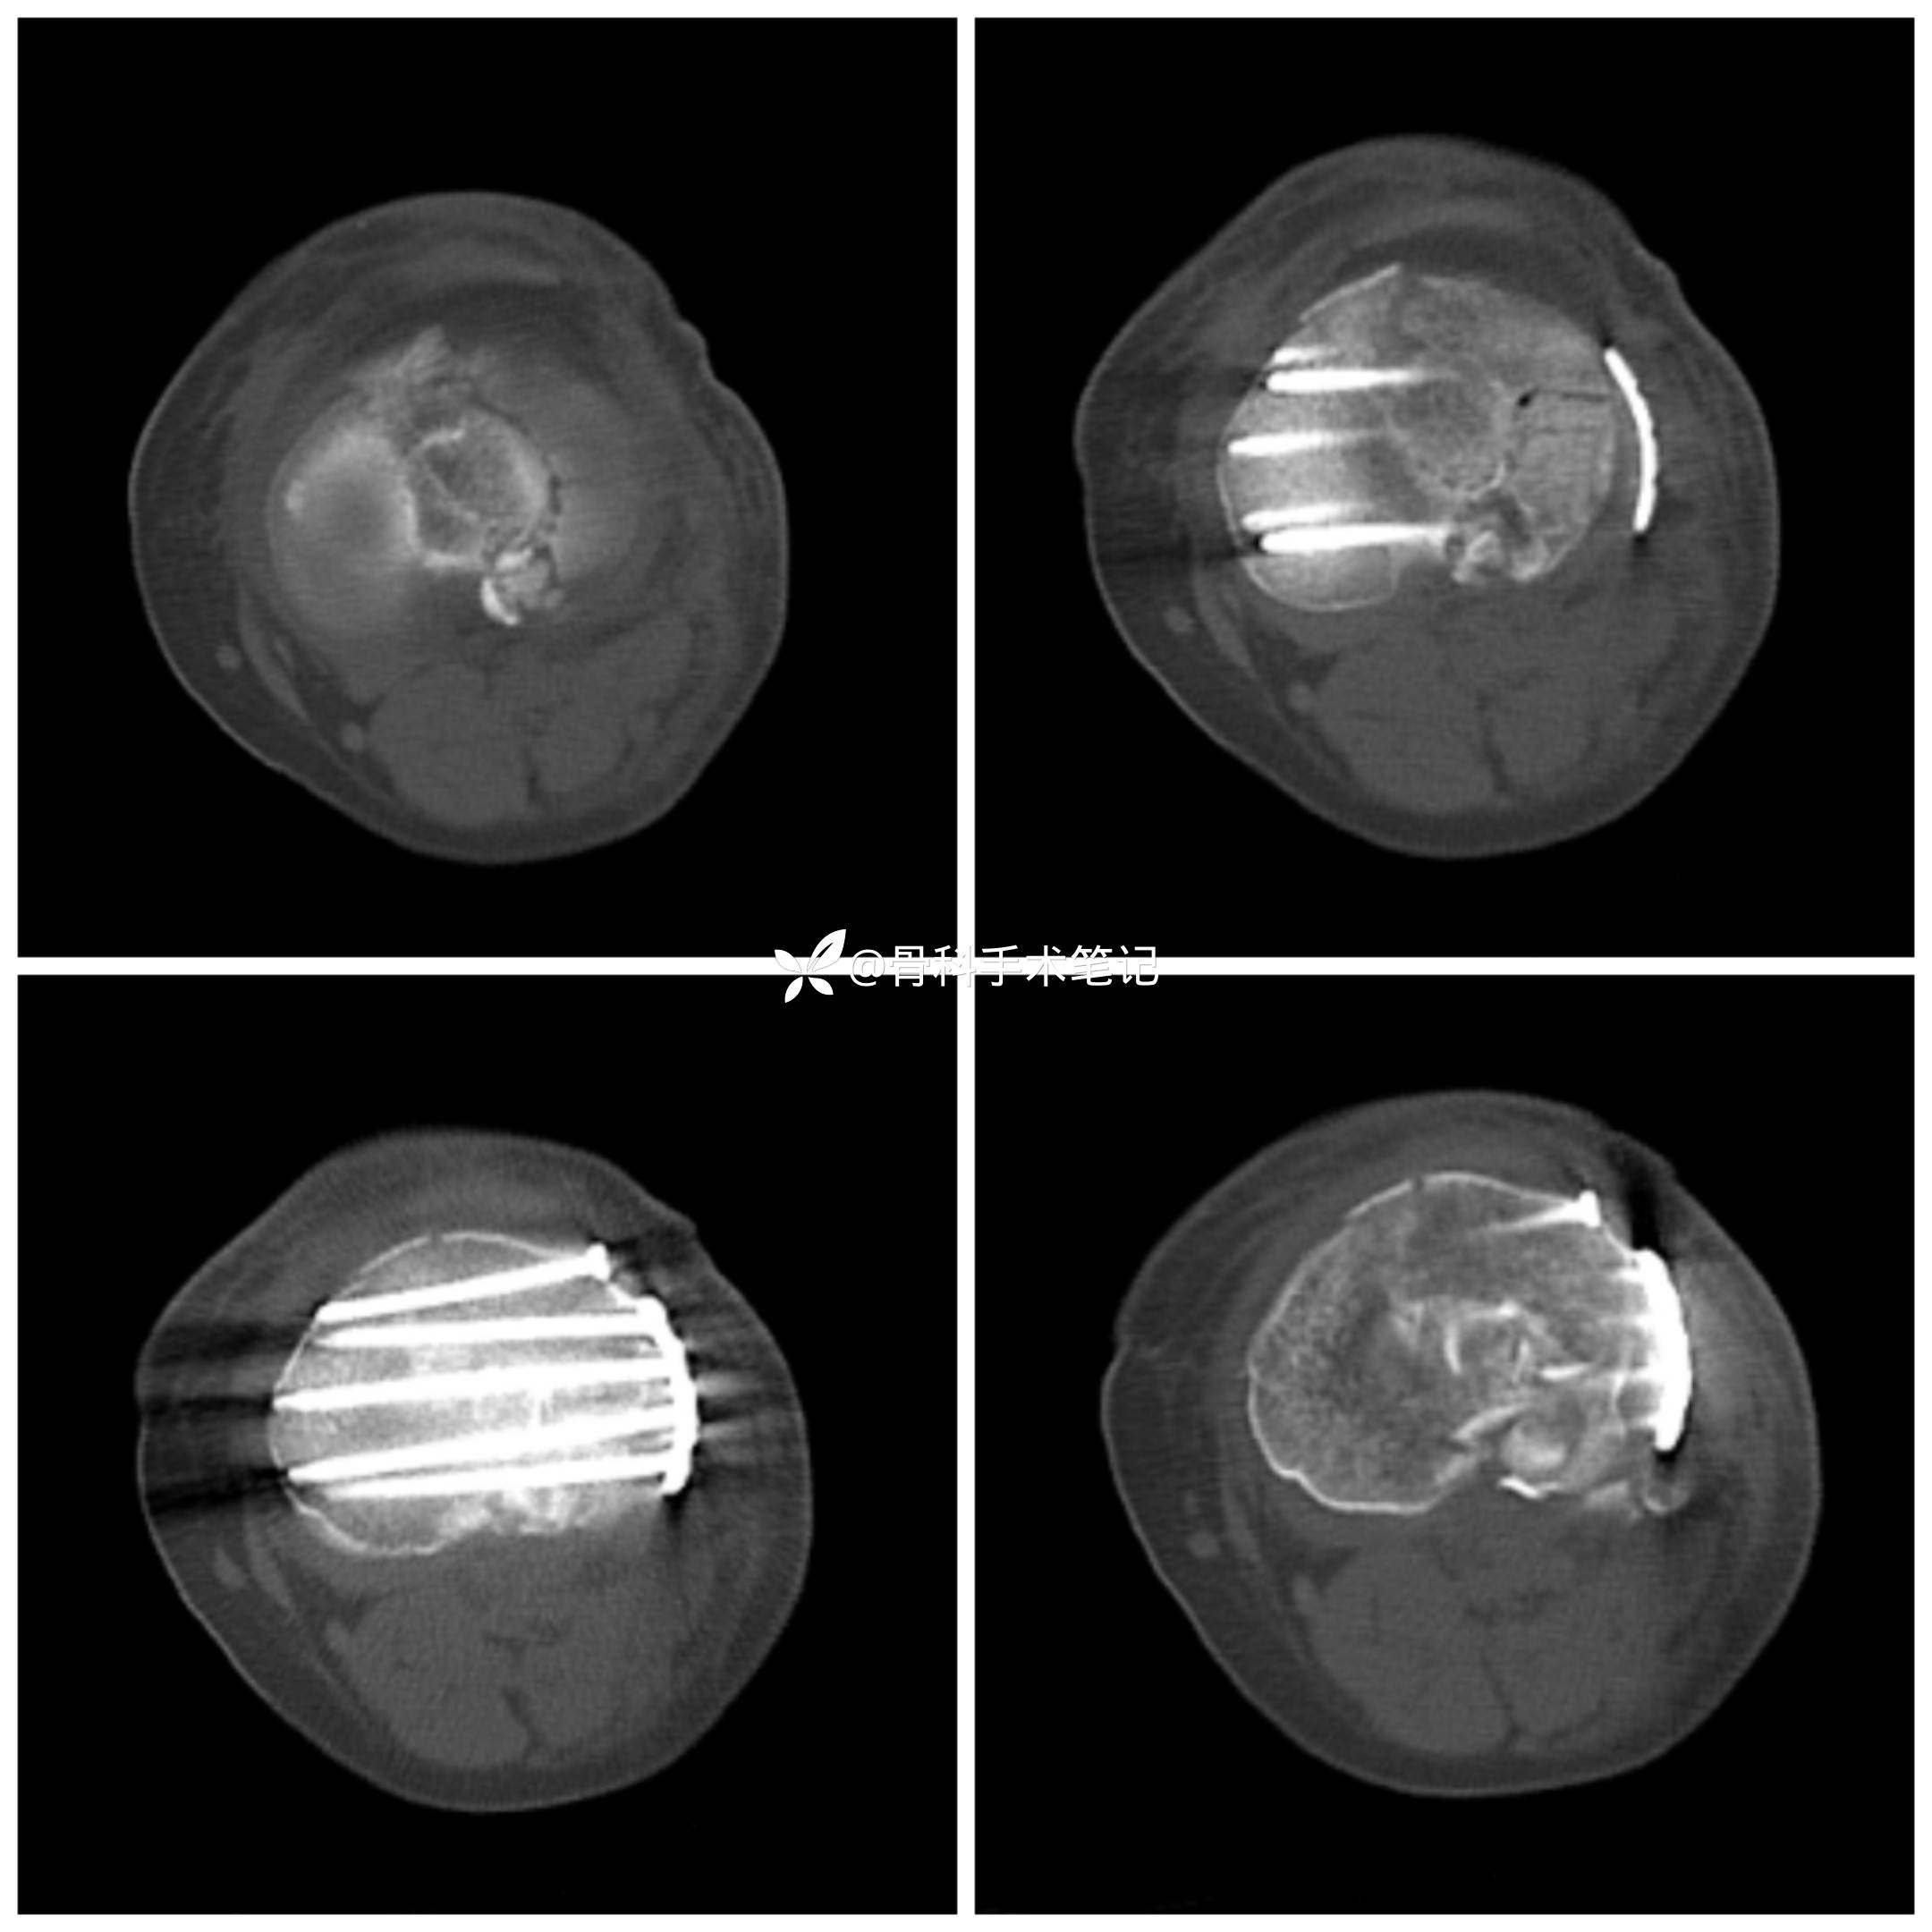

【临床诊断】:1.左胫骨平台粉碎性骨折;2外侧半月板损伤。

外侧切口→撑开器撑开→缝合修复外侧半月板→外侧开窗复位塌陷的关节骨块克氏针临时固定这→取髂骨植骨支撑→外侧排钉钢板固定。

术后影像资料